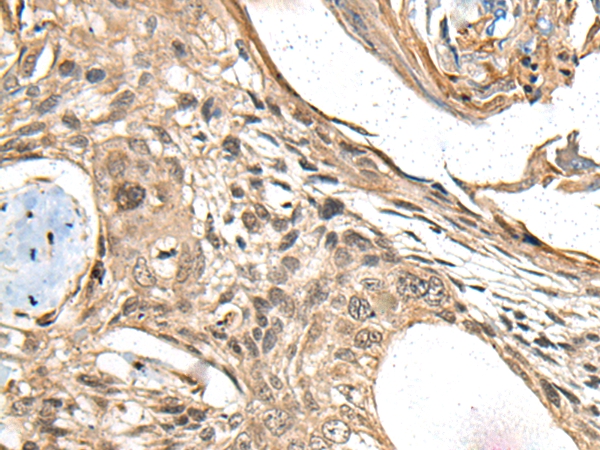

The image on the left is immunohistochemistry of paraffin-embedded Human liver cancer tissue using 46605(MAPK4 Antibody) at dilution 1/35, on the right is treated with synthetic peptide. (Original magnification: x200)

The image on the left is immunohistochemistry of paraffin-embedded Human esophagus cancer tissue using 46605(MAPK4 Antibody) at dilution 1/35, on the right is treated with synthetic peptide. (Original magnification: x200)